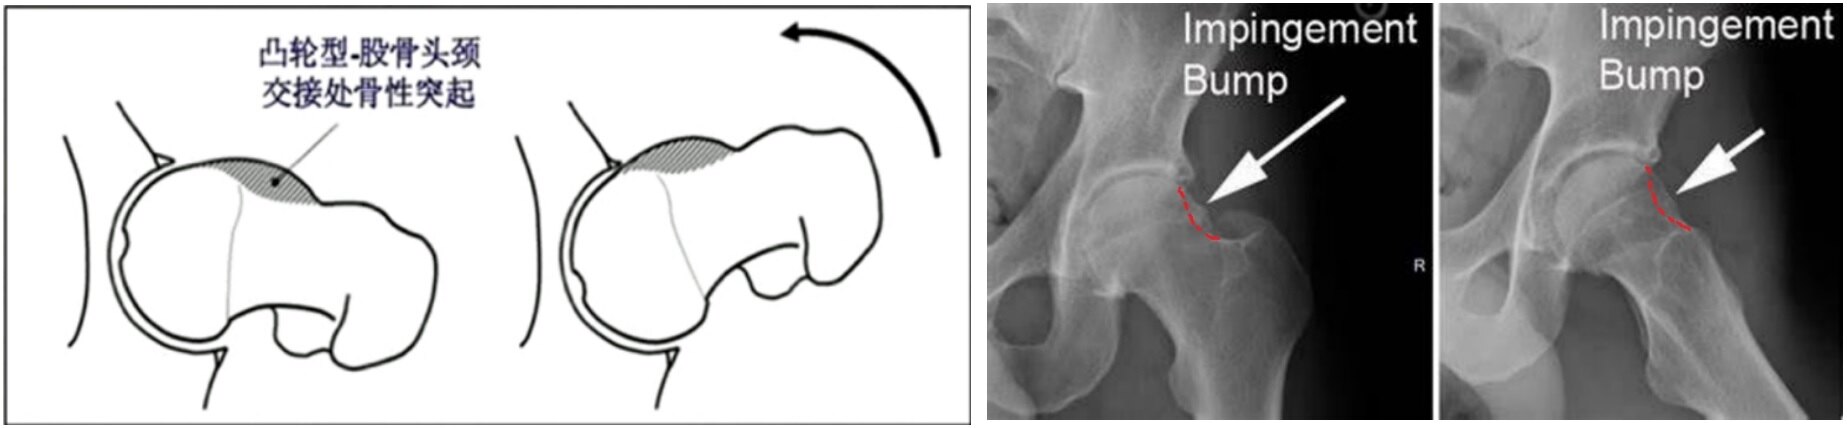

① 凸轮型(cam-type): 股骨头颈交界处异常隆起,屈曲时股骨头颈撞击髋臼缘。

图6.髋关节撞击可由股骨头颈交界处骨质异常隆起造成(凸轮型Cam)。

① 凸轮Cam:A. 手枪柄样畸形

图10.双髋正位X线片可看到股骨头颈“手枪柄”样隆起。

B. α角增大> 50°(45°Dunn位)

图11.患髋45°Dunn位X线片可看到股骨头颈α角增大> 50°。